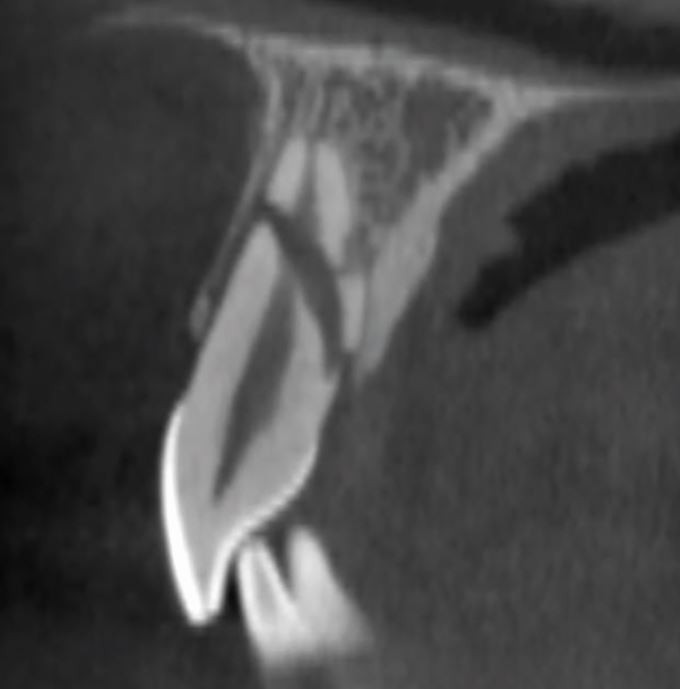

Delays in treatment may occur from athlete behaviour (late arrival, underestimating urgency, uncooperativeness) and healthcare factors (staff knowledge, accident and emergency department waits, triage). Effective care follows three phases: acute (within three hours), subacute (24 hours), and delayed (over 24 hours), as categorised by Andreasen et al.,43 to be followed alongside IADT guidelines34,35,36,37 for structured management (Table 3; Figures 10, 11, 12, 13, 14, 15, 16 and 17).

A CBCT scan of a root fracture, seen in the sagittal plane

A CBCT scan of a dento-alveolar fracture extending over three maxillary incisor teeth, seen in the axial (A) and sagittal (B) planes